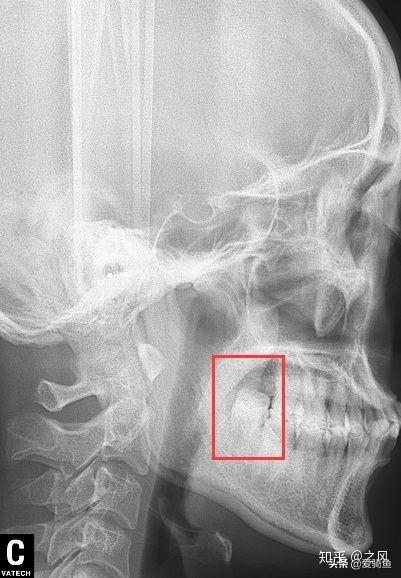

排隊等待叫號,進去后張嘴檢查下,讓去拍片子,應該就是我之前去的其他牙診所機構的口掃,這里沒有給我電子照片,下面是以前拍的。

口掃

智齒